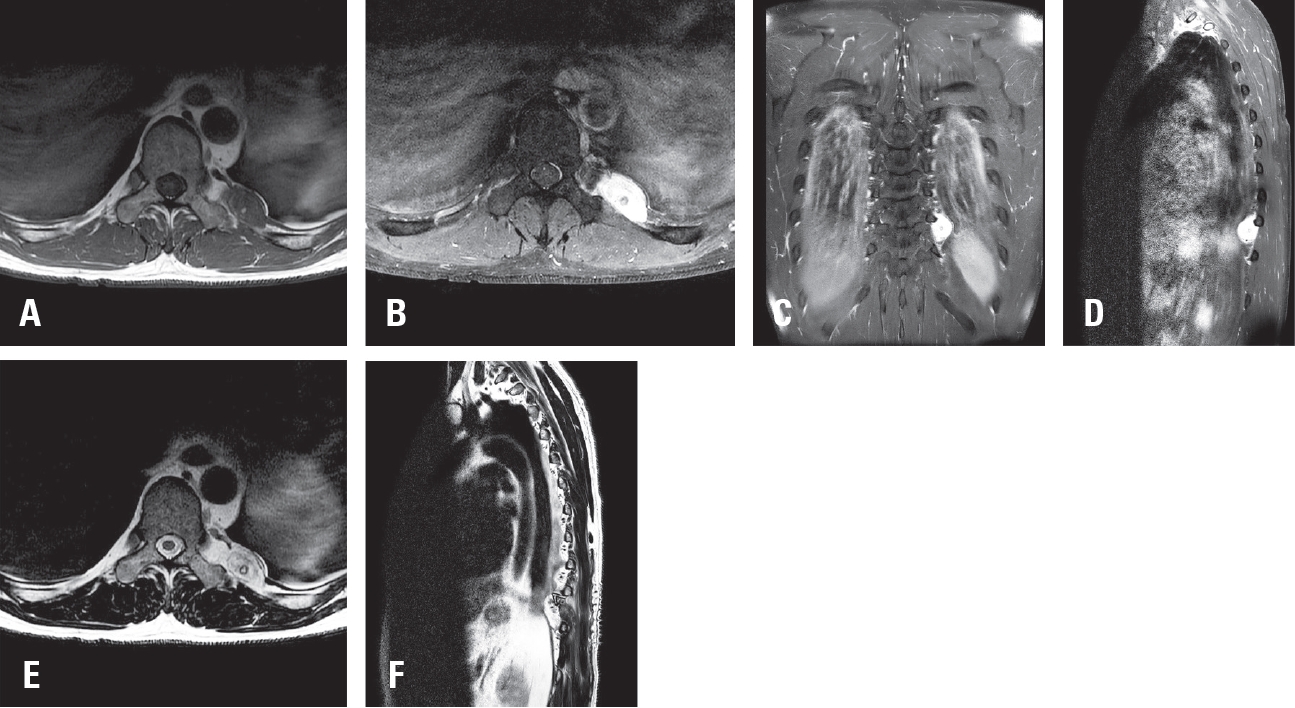

Tethered cord syndrome (TCS) is a condition in which the spinal cord becomes pathologically stretched due to various congenital or acquired etiologies, leading to progressive neurological symptoms. While surgical detethering is the gold standard for pediatric patients, adult-onset recurrent TCS presents a significant surgical challenge. Reoperation carries substantial risks—including spinal cord injury, cerebrospinal fluid leakage, and a high rate of retethering—often resulting in suboptimal long-term outcomes. Recently, spine-shortening osteotomy (SSO) has emerged as an alternative technique to reduce spinal cord tension without direct manipulation of the neural elements. Here, we report a case of recurrent adult TCS associated with a lipomyelomeningocele, which was exacerbated by post-traumatic kyphosis from an L1 compression fracture. The patient was successfully treated with SSO at the L1 level. This case highlights the utility of SSO as a safe and effective alternative to conventional revision detethering, particularly in complex cases involving spinal deformity.

Spine-Shortening Osteotomy for Recurrent Adult Tethered Cord Syndrome Exacerbated by Traumatic Kyphosis: A Case Report

Seohong Min, Jae Min Kim, Dongkyu Kim, Bongju Moon, Jeong-Yoon Park, Kyung Hyun Kim, Sung-Uk Kuh, Dong-Kyu Chin, Keun-Su Kim, Hyun-Jun Jang

J Adv Spine Surg 2025;15(2):119-124.   Published online December 31, 2025

DOI: https://doi.org/10.63858/jass.15.2.119